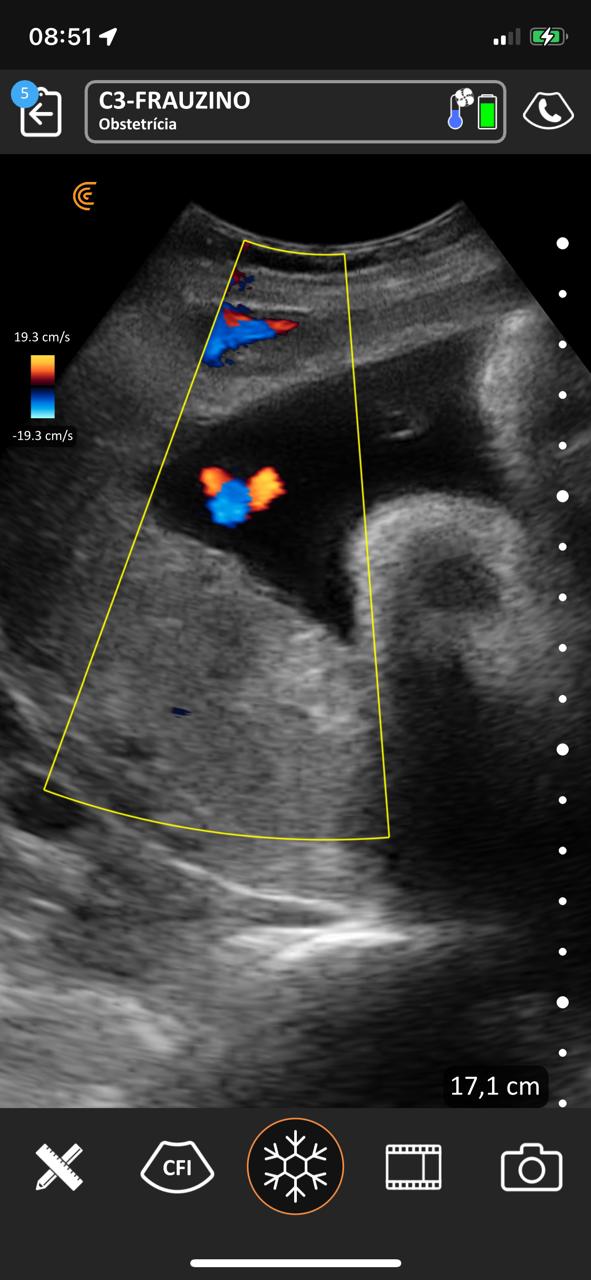

No período compreendido entre 07/03/2023 a 07/03/2025 na Estratégia de Saúde da Família São Francisco ESF-03 e Sol Nascente ESF-07 no município de Porangatu (GO), Brasil realizou-se um total de 8.349 atendimentos médicos, com 769 consultas de pré-natal e 411 ultrassons no local de atendimento de acompanhamento do pré-natal de risco habitual com aparelho portátil de bolso, sem fio, tecnologia Clarius C3 HD3, transdutor convexo, frequência de 2-6 MHz e monitores iPhone-10 e iPad Air 11. Acompanharam alguns atendimentos 12 bolsistas do PMpB dos municípios goianos Bonópolis, Britânia, Campinorte, Mara Rosa, Mundo Novo, Mutunópolis, Niquelândia, Nova Veneza, Santa Tereza de Goiás, São Miguel do Araguaia e do Pará Santana do Araguaia. Os bolsistas não tinham conhecimentos prévios sobre a PoCUS, disseram que sua formação nessa ferramenta durante o PMpB foi satisfatória e caso tivessem um aparelho sentem confiança em realizar o procedimento tanto na Unidade Básica de Saúde quanto nos domicílios, acreditaram que a formação básica recebida foi alcançada e concordam totalmente que a ultrassonografia no local de atendimento poderia estar dentro da formação especializada em medicina de família e comunidade e entenderam que no pré-natal de risco habitual é uma ferramenta que pode mudar sua conduta.

Nos acompanhamentos das consultas de pré-natal, dos 411 ultrassons realizados, 19 foram de diagnóstico gestacional e datação da idade gestacional, sendo 13 com idade gestacional menor de 14 semanas, uma na 24ª e outra na 29ª semana. Houve duas gestações gemelares que foram acompanhadas conjuntamente com o alto risco. A média de idade das gestantes foi de 26 anos e o da idade gestacional de 22 semanas e 2 dias. Os bolsistas realizaram um total de 188 ultrassons e após a familiarização teórica e prática, foram capazes de identificar 10 tópicos como situação, apresentação, dorso, batimento cardíaco fetal, movimentos fetais, órgãos internos (ao menos 1 estrutura), biometria (ao menos diâmetro biparietal e comprimento do fêmur), placenta, líquido amniótico, cordão umbilical, datar e descrever o procedimento.